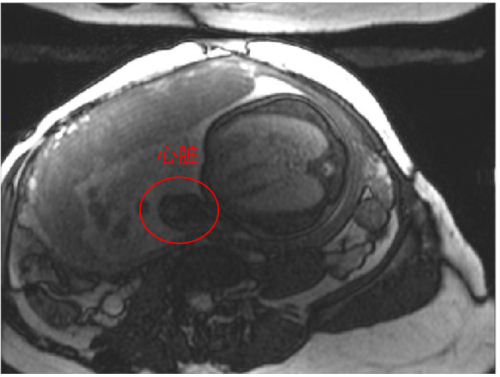

磁共振胎儿成像可发现复杂先天性疾病,尤其对神经发育异常和心血管疾病诊断有不可替代的价值。现有磁共振技术在成像速度和图像信噪比方面对于胎儿成像有较大的局限性。团队基于高灵敏电子设计了大范围、高密度多通道新型表面柔性线圈,与商用的线圈对比,设计的线圈的图像信噪比提高可达40%左右,更多的线圈单元可以显著提高成像速度,成功实现了清晰的胎儿大脑(2倍加速)和心脏电影(4倍加速)成像。相关成果发表在IEEE Transactions on Medical Imaging,第一作者为陈巧燕,通讯作者为郑海荣、李烨。

图3 设计的36通道线圈(结合12通道脊椎线圈)采集的胎儿心脏成像(4倍加速)结果。